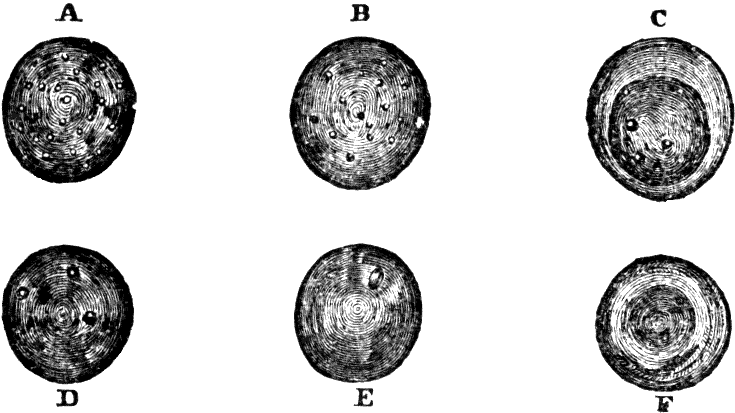

[pg 19]All living bodies are made up of tissues. There is no part, no organ, however soft and yielding, or hard and resisting, which has not this peculiarity of structure. The bones of animals, as well as their flesh and fat, are composed of tissues, and all alike made up of cells. When viewed under a microscope, each cell is seen to consist of three distinct parts, a nucleolus, or dark spot, in the center of the cell, around which lies a mass of granules, called the nucleus; and this, in turn, is surrounded with a delicate, transparent membrane, termed the envelope. Each of the granules composing the nucleus assimilates nourishment, thereby growing into an independent cell, which possesses a triple organization similar to that of its parent, and in like manner reproduces other cells.

Fig. 4. Nucleated cell.

From Goeber. 1. Periphery of the cell, or cell-wall. 2. Nucleus. 3.

Nucleolus in the center.

Various opinions have been entertained in regard to the formation, or growth, of bone. Some anatomists have supposed that all bone is formed in cartilage. But this is not true, for there is an intra-membranous, as well as an intra-cartilaginous, formation of bone, as may be seen in the development of the cranial bones, where the gradual calcification takes place upon the inner layers of the fibrous coverings. Intra-cartilaginous deposit is found in the vicinity of the blood-vessels, within the cartilaginous canals; also, there are certain points first observed in the shafts of long bones, called centers of ossification. These points are no sooner formed than the cartilage corpuscles arrange themselves in concentric zones, and, lying in contact with one another, become very compact. As ossification proceeds, the cup-shaped cavities are converted into closed interstices of bone, with extremely thin lamellæ, or layers. These, however, soon increase [pg 21]in density, and no blood-vessels can be observed within them.

Fig. 7. Vertical section of

cartilage near the surface of ossification. 1. Ordinary appearance

of the temporary cartilage. 1'. Portion of the same more highly

magnified. 2. The cells beginning to form into concentric zones.

2'. Portion more magnified. 3. The ossification is extending

in the inter-cellular spaces, and the rows of cells are seen resting in the

cavities so formed, the nuclei being more separated than above. 3'.

Portion of the same more highly magnified.